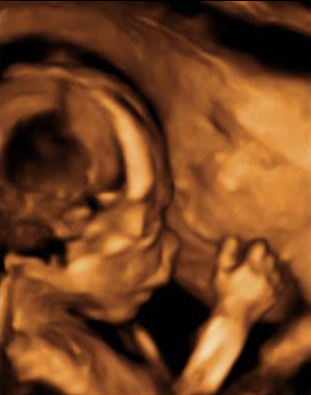

En la ecografía podemos ver una hernia intestinal (u onfalocele), lo que significa que parte del intestino del feto está fuera del abdomen. Observamos la sección transversal del abdomen fetal. A la izquierda, contenido intestinal (entre marcas de medición) herniado fuera del abdomen, debido a un defecto en la inserción del cordón umbilical, que se marca en la imagen con una estrella (*).

Onfalocele o intestino del feto fuera del abdomen